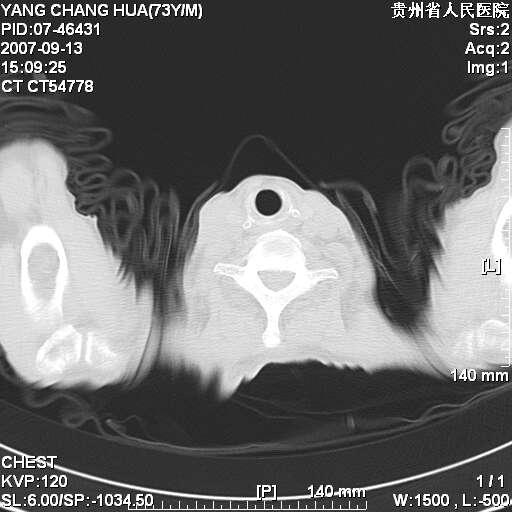

食管癌未除。

双肺散在斑片状及多发小结节状阴影,边缘模糊,双上肺野明显,双侧胸膜腔少量积液,纵隔及肺门区未见明显肿大淋巴结,肝脾肿大,脾内见多发低密度区,结合临床考虑恶性淋巴瘤(肺内表现为肺炎肺泡型),单看影像表现,肺结核不能排除。建议结合实验室检查或表浅淋巴结活检。